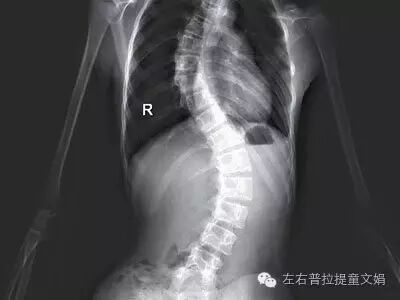

从形态来分,则分为C型侧弯和S型侧弯。

三、手术治疗

适用于脊椎侧弯的角度大于45度时,则必须考虑以手术的方式来加以矫正,避免因脊椎侧弯的角度太大,影响呼吸及心脏的功能。